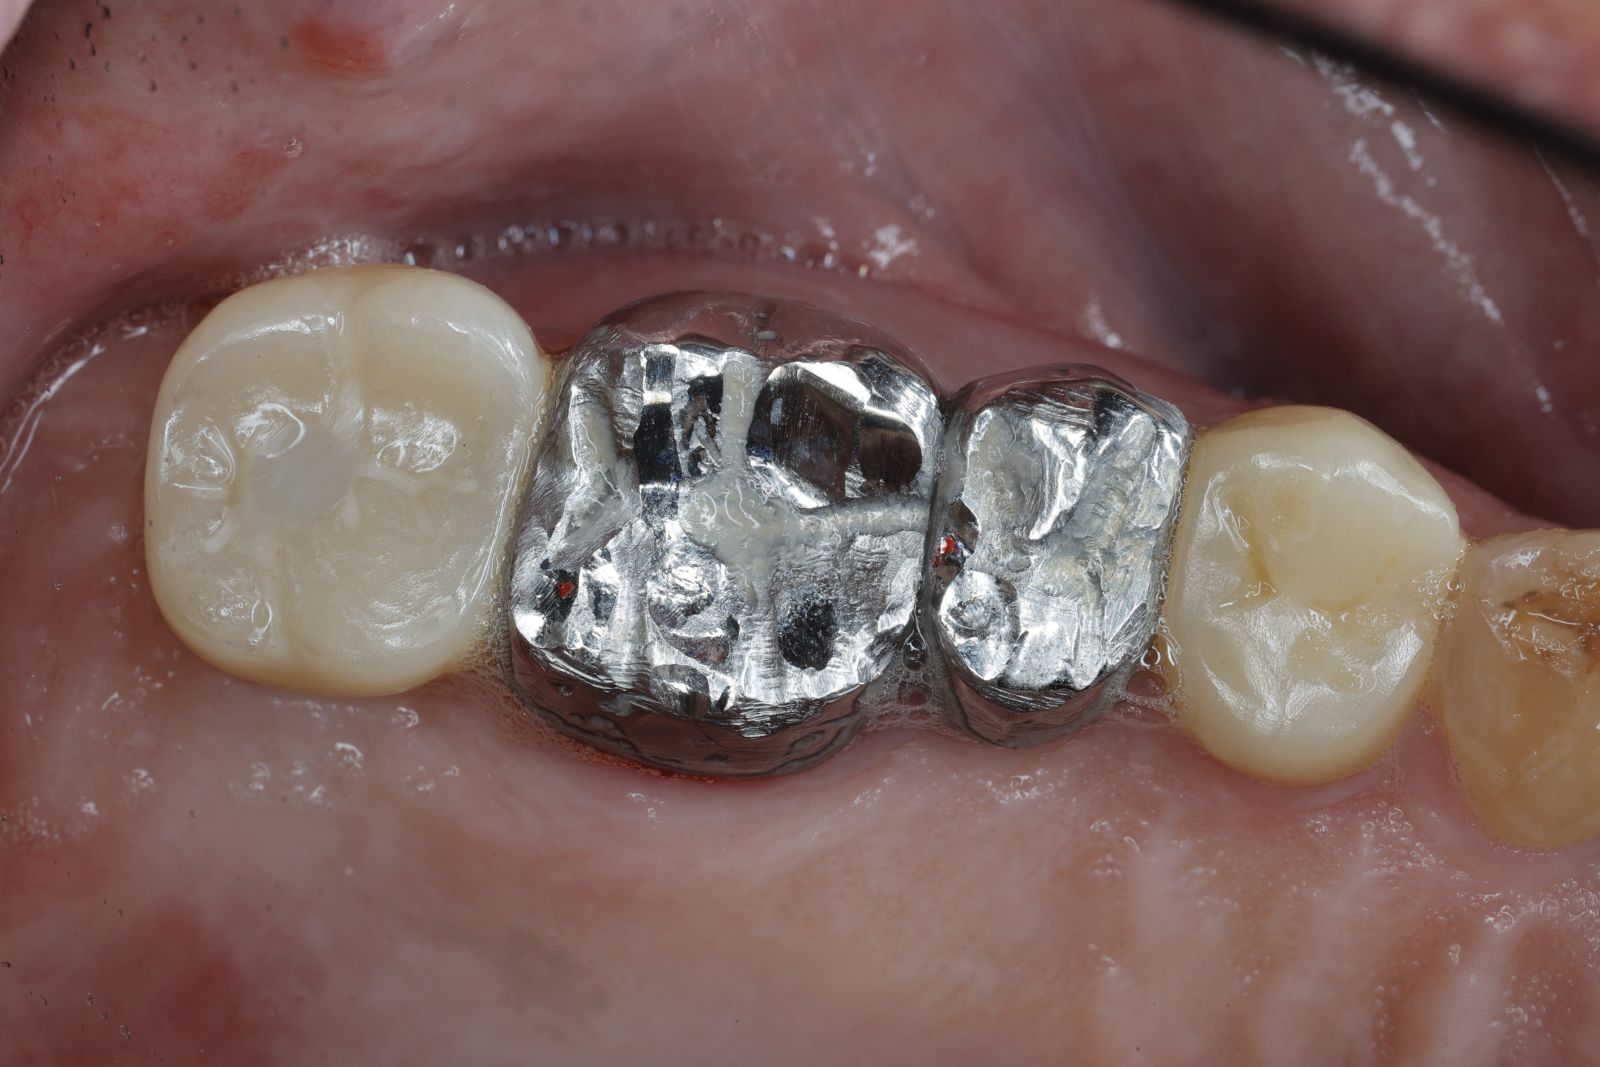

【 案 例 二】

- 手術過程,在植入植體前先用導板定位,確認植牙位置及角度。

- 手術中先使用導板定位,確認植牙角度及位置

- 藉由導板的定位,無須劃開傷口,精準的植入植體。

- 植入植體後不用劃開傷口無須縫合,鎖上癒合帽等待骨整合完成,過程輕鬆舒適。

- 3-4個用即可裝上全瓷牙冠恢復咬合功能